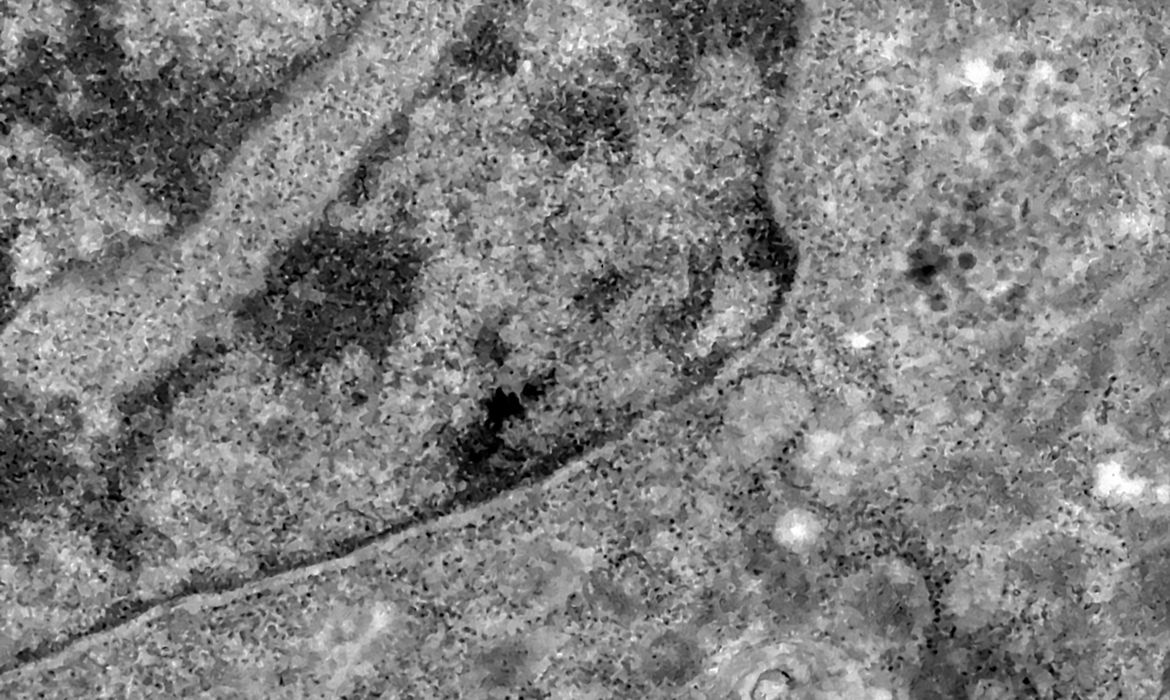

(Foto: Reprodução/Agência Brasil)